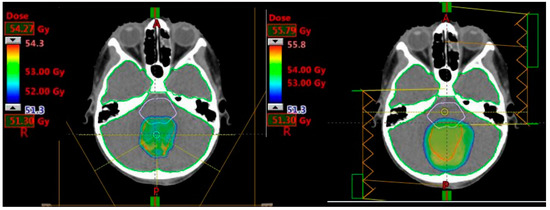

2.2.1. Prescribed Dose and Beam Arrangement for Intensity-Modulated Proton Therapy (IMPT)

2.2.2. Prescribed Dose and Beam Arrangement for Intensity-Modulated Photon Therapy (IMRT)

3.1. Medulloblastoma

3.2. Supratentorial Ependymoma